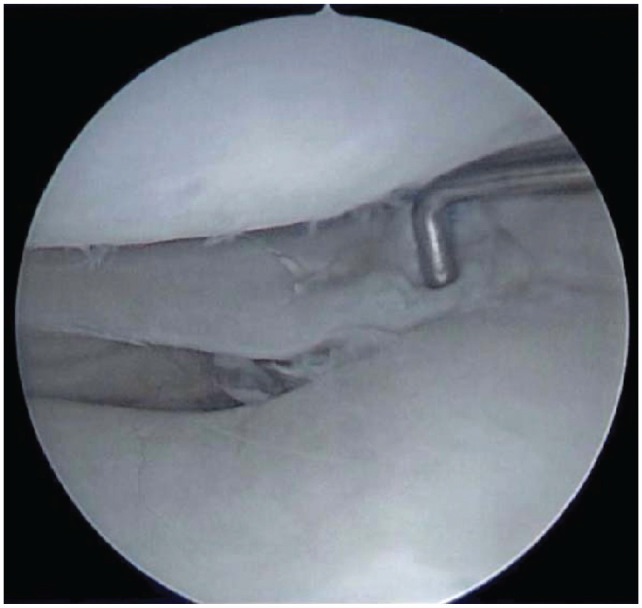

Background: Lateral meniscal oblique radial tears (LMORTs) of the posterior horn typically occur in the setting of an acute anterior cruciate ligament (ACL) rupture. Despite publications pertaining to the prevalence, biomechanics, and surgical repair techniques of LMORTs, studies reporting mid-term outcomes after LMORT repair are lacking.

Methods: A retrospective chart review was conducted on 845 patients who underwent a meniscal repair at The Ohio State University Sports Medicine Center from 2017 to 2019. Operative reports and images were manually reviewed to identify LMORTs occurring concomitantly with ACL rupture. Subsequent knee surgery, meniscal repair failure, and postoperative complications were identified, with failure defined as retear at the same meniscal site. Patients without at least 2 years of follow-up were excluded. Patients were contacted postoperatively for evaluation of patient-reported outcomes (PROs)-including the Knee injury and Osteoarthritis Outcome Score (KOOS), Marx activity rating scale (Marx), and pain on a visual analog scale (VAS).